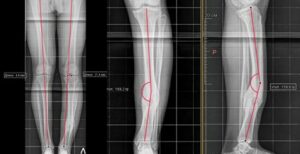

- Correction of post-traumatic deformation of the leg bones using the Ilizarov apparatus.